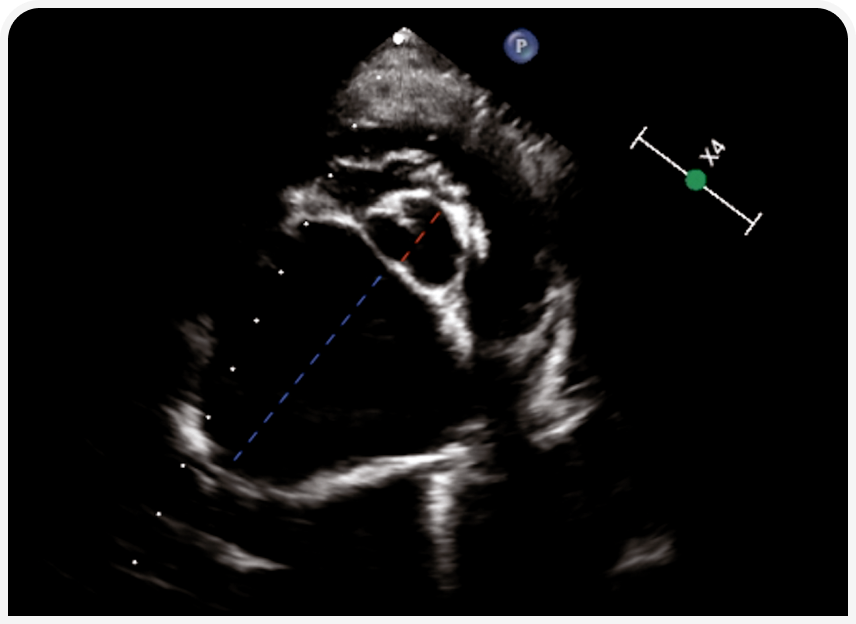

Если доступно ультразвуковое исследование, желательно измерить диаметры левого предсердия и корня аорты, чтобы рассчитать соотношение и таким образом оценить размер этой камеры сердца; если значение больше 1,6, выше вероятность увеличения левого предсердия из‑за возможного заболевания сердца (Рисунок 3) (5). При одышке, повышенной температуре и слизисто-гнойных выделениях из носа выше вероятность пневмонии, и следует эмпирически начать прием антибиотиков.

Рентгенография органов грудной клетки — основной метод диагностики у собак с заболеваниями легочной паренхимы (Рисунок 4), так же используется «прикроватное» УЗИ (POCUS), если это возможно, и эхокардиографией, если в списке дифференциальной диагностики высока вероятность заболевания сердца (Рисунок 5). В ожидании первоначального диагностического обследования можно рекомендовать компьютерную томографию органов грудной клетки и эндотрахеальный лаваж. По их результатам решают, следует ли ограничить лечение ингаляцией кислорода или нужно добавить антибиотики, диуретики, стероиды, бронходилататоры.